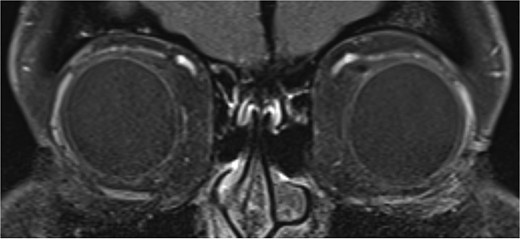

Initial magnetic resonance imaging (MRI) of the brain and orbits with contrast was normal (Fig. 2). However, the patient’s symptoms were suspicious for acquired Brown syndrome associated with an inflammatory etiology. As such, she was trialed on regular ibuprofen 400 mg three times daily.

T1 coronal image of orbits which shows normal symmetrical superior obliques.